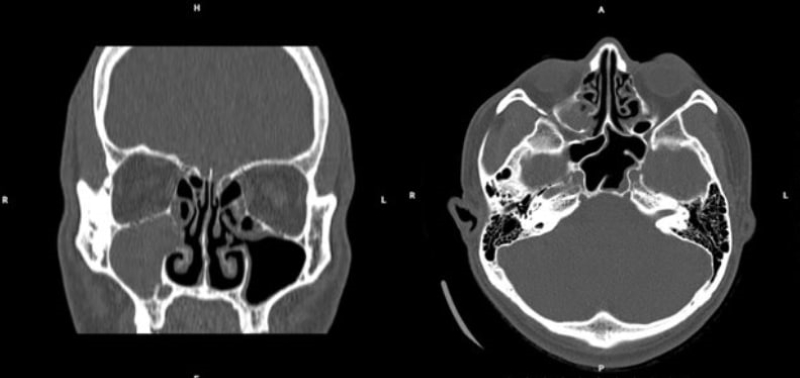

Hình ảnh chụp cắt lớp vi tính xoang cho thấy tình trạng viêm đa xoang mức độ III theo phân độ Lund-Mackay. Đặc biệt, kết quả nuôi cấy và định danh vi khuẩn xác định tác nhân gây bệnh là Haemophilus influenzae - một trong những vi khuẩn thường gặp gây viêm xoang cấp mủ.

Hình ảnh chụp cắt lớp vi tính xoang phát hiện tình trạng viêm đa xoang mức độ III